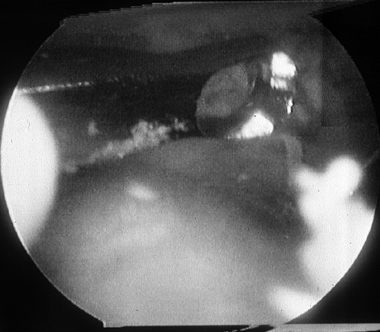

The surgical findings generally include synovitis and fibrosis in the

similar to the meniscoid lesion, as described by Wolin et al. (77) (Fig. 93.9).

|  |

| Figure 93.9. Viewed from the anteromedial portal, anterolateral soft-tissue impingement with fibrosis and synovitis can be seen. (From Ferkel RD, Scranton PE Jr: Arthroscopy of the Foot and Ankle. J Bone Joint Surg Am 1993;75:1233. Copyright 1993 by The Journal of Bone and Joint Surgery, Inc., reprinted with permission.) |